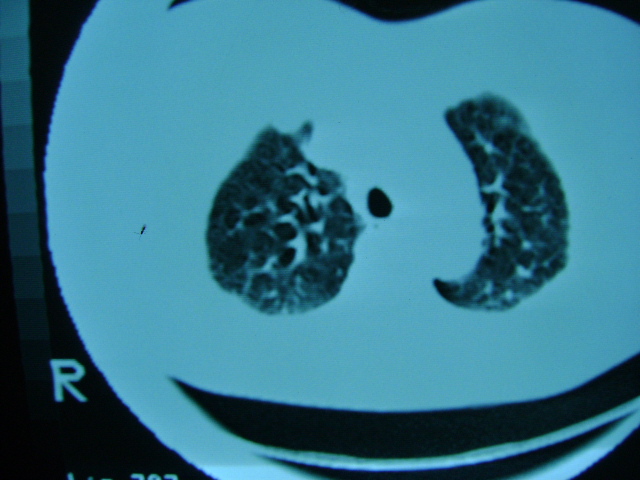

朋友的母亲,56y,咳嗽三个月,感觉左肺门不对,请大家给点意见

肺内应该存在感染

慢支 !不放心可追踪复查。

左肺门未见异常‘右肺有少许感染,图象质量不好

扫描所示未见明显异常!建议结合临床